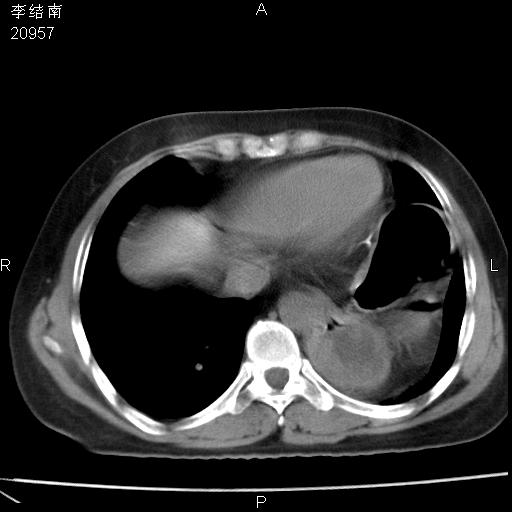

患者女,45岁,以右侧腰部包块来就诊,局部有压痛,皮肤颜色正常。因为是熟人扫的范围较大,患者有胆结石,胆源性胰腺炎病史。请大家看看,有手术病理。

可能大家觉得片子的质量不好,当时是做下腹部扫描,所以没有常规喝水,右腹壁的病灶当时是,密度不均有钙化影,局部骨质没见破坏,肝脏应该是受压的表现,所以当时考虑为腹壁的良性占位,各位老师考虑的神经源性肿瘤,我当时还真没想到,胰腺是胰腺炎治疗后改变.膈脚旁的混杂密度包快不好考虑什么,到上级医院做增强(腹部)+肺部平扫后,发现腹壁的病灶呈不均匀性强化局部可见囊性灶,当时考虑为腹壁结核,最具戏剧性的是膈脚旁的混杂密度灶确是胃的一部分,而腹壁的病灶确是脂肪瘤(简直不可思议)但是我亲眼所见在我们县医院开的.

很不好意思 ,患者后来手术切口裂开,临床医生作了病理证实是腹壁结核。

[病理诊断] CT13183腹壁结核!